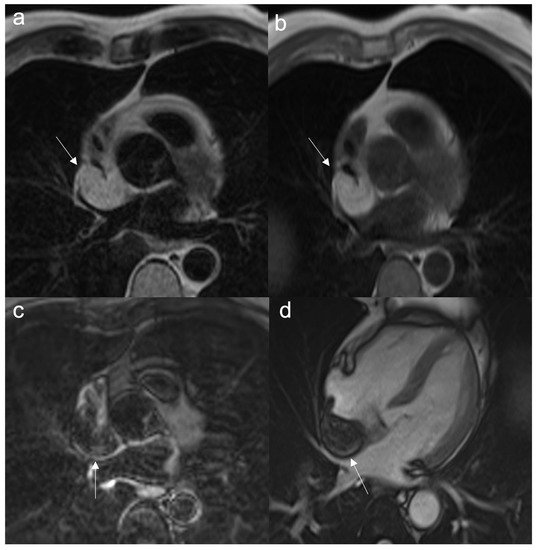

- To assess border, size, and location

- Very useful for stable anatomical relationships of the mass with myocardium (intramyocardial or pedunculated) and with adjacent structures

- To evaluate mobile masses, such as atrial myxomas or papillary valve fibroelastoma

- To reveal pericardial effusion